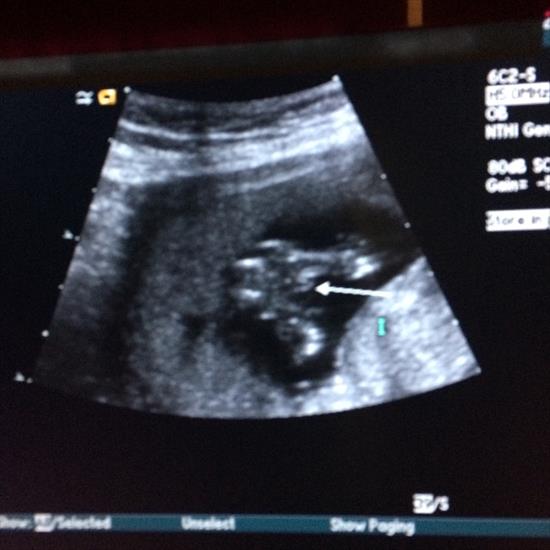

I'll add all of the photos I have. A leg isn't showing in the potty shot so I drew it in for a better idea. i just can't believe that this could be a boy - it looks nothing like any others I've seen. What are your thoughts? Would you announce going off of these images?

Attachment 28149Attachment 28153Attachment 28150Attachment 28151